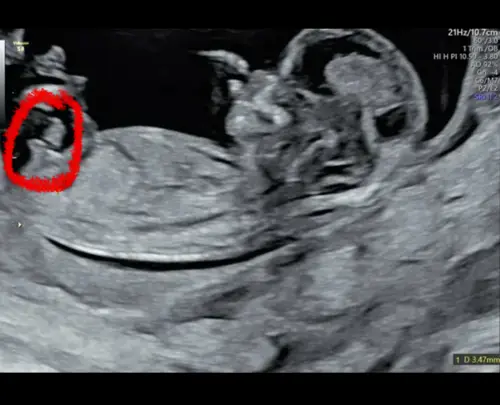

Eerste zie je niks. Deze echo is een jongen! 💙

Dat is echt geen jongen dat is een meisje 😉 dat is de clitoris die je ziet